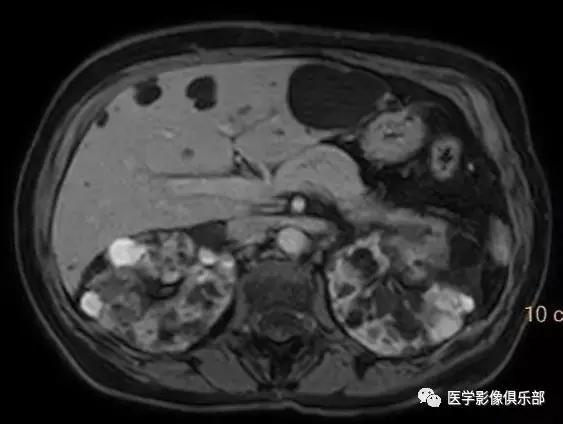

[典型病例一]:60岁,女性患者,肾功能损害。

双侧肾脏体积增大,皮质及髓质内能够看到多发大小不等的囊肿,大部分囊肿T1WI呈低信号,T2WI像上呈高信号,有少部分囊肿在T1WI呈高信号的复杂囊肿表现,可能由于里面含有不同时期的出血及高蛋白有关,肝脏内也可见较多数量的囊肿。